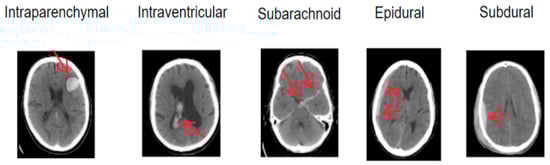

1. Introduction